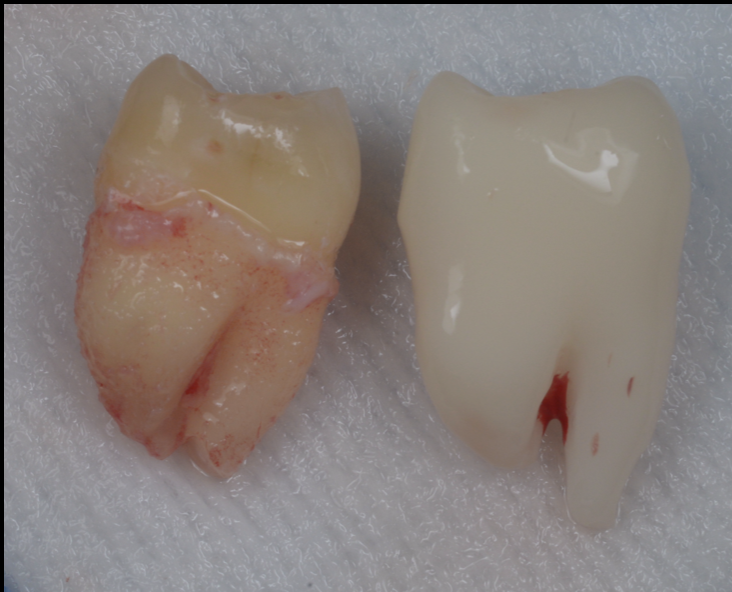

移植の成否を左右する要素の一つが、移植歯が口の外に出ている時間(口腔外時間/extra-alveolar time)です。歯根膜細胞は乾燥や機械的損傷に弱く、時間が延びれば延びるほどリスクが上がります。

臨床でも「短く、湿潤を保ち、触りすぎない」が原則です。

つまり、移植の難しさは「外科的に入れること」ではなく、歯根膜のダメージを最小化しながら“適合させきること”にあります。

近年注目されているのが、CTデータからドナー歯の3Dレプリカ(模型)を作成し、移植床形成・適合を事前に詰めておく方法です。

狙いは明確です。

- 移植床の形成をレプリカで完結させる

- 実歯(ドナー歯)を抜いた後は、最小回数・最短時間でフィットさせる

- 口腔外時間を短縮し、歯根膜への機械的損傷を減らす